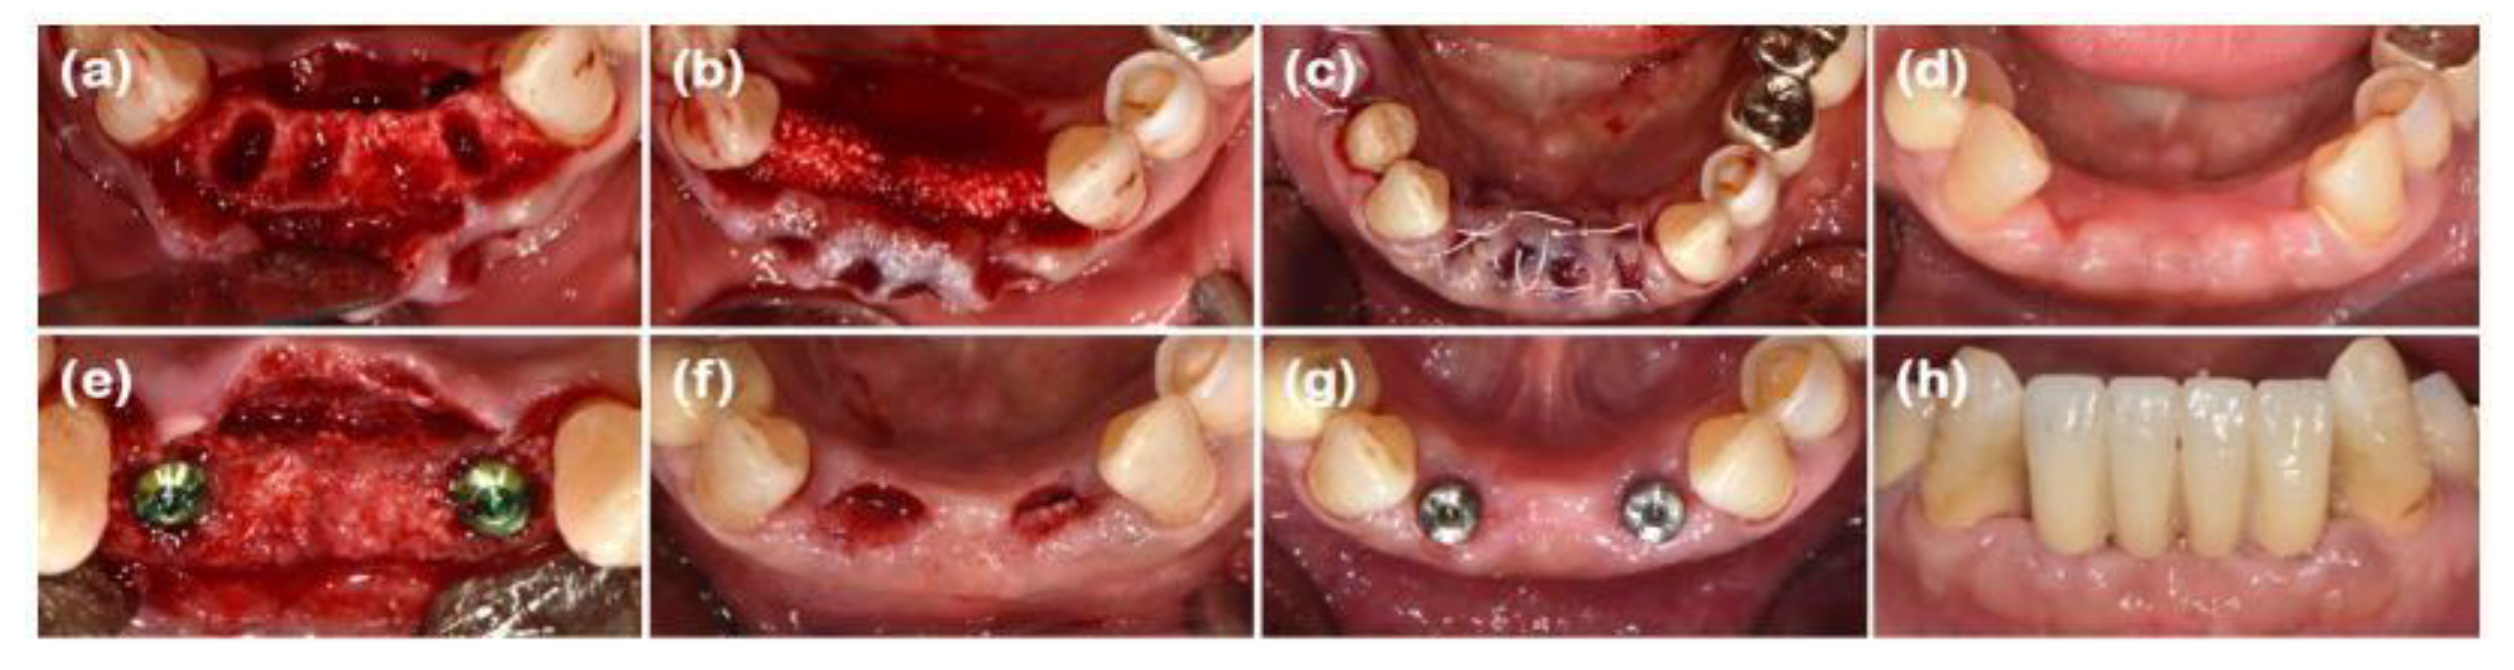

After performing full-mouth scaling, #23 was extracted and ARP was performed a month later. A horizontal incision was made on the palatal side, and a full-thickness flap, including the interdental papilla, was elevated buccally. The periapical cystic lesion was removed, revealing extensive horizontal and vertical bone defects as well as buccal bone plate loss (Figure 1b). A synthetic bone graft material mixed with collagen (Osteon 3 collagen® (biphasic calcium phosphate with collagen), Genoss Co. Ltd., Suwon, Korea) was inserted into the extraction socket, and to fully cover the alveolar crest, a resorbable collagen membrane with soft-type stiffness (Collagen membrane 2®, Genoss Co. Ltd.) was applied. To reconstruct the buccal bone wall, a resorbable collagen membrane with medium-type stiffness (Collagen membrane P®, Genoss Co. Ltd.) was placed over the buccal side of the socket. Due to the extensive buccal bone loss, a soft tissue graft between the membrane and the flap was necessary to compensate for soft tissue collapse and delayed healing. A xenogenic collagen matrix (Collagen graft 2®, Genoss Co., Ltd.) was inserted buccally and slightly on the crestal area (Figure 1c,d). The area was sutured without tension using 6-0 Vicryl (Ethicon, INC., a Johnson & Johnson company, Somerville, USA) and 5-0 Black nylon (AILEE Co., Ltd., Busan, Korea), and intentional secondary healing (open healing) was induced. Upon suture removal 10 days later, secondary healing was observed, with no significant findings other than partial exposure of the bone graft material on the buccal side. The secondary healing area was continuously monitored. After confirming the epithelialization of the soft tissue and the complete regeneration of the interdental papilla between the adjacent teeth, the first implant surgery was performed 9 months after the alveolar ridge augmentation. Prior to implant placement, the width and height of the remaining alveolar ridge were observed to be in good condition (Figure 1e and Figure 2b). A full-thickness flap was elevated, revealing a sufficiently augmented alveolar bone with a width of approximately 6 mm bucco-palatally. The implant was placed in an ideal position (Superline Φ3.5×10 mm, Dentium, Seoul, Korea), and to compensate for the loss of bone graft material due to drilling, additional guided bone regeneration (GBR; Osteon 3 collagen® and Collagen membrane P®, Genoss Co., Ltd.) was performed on the palatal side (Figures 1f and 2c). Five months after the first implant surgery, the second implant surgery was carried out (Figure 1g and 2d). Seven months after the first implant surgery, a customized abutment and veneered zirconia were placed. The interdental papilla between #22 and #23 was regenerated, and 4 mm of buccal keratinized mucosa was stably observed (Figure 1h).

Figure 1. Clinical photographs of case 1. (a) Initial presentation of the maxillary left canine prior to extraction. (b) Buccal bone defect exposed after full-thickness flap elevation. (c) Defect filled with deproteinized bovine bone mineral (DBBM). (d) Bone graft area covered with soft-type resorbable collagen membrane, hard-type resorbable collagen membrane on the buccal side, and finally, collagen matrix in the outer position. (e) Full-thickness flap elevation reveals adequate bone volume. (f) Implants placed in the sufficiently augmented bone area. (g) Second implant surgery performed. (h) Definitive prosthesis connection.